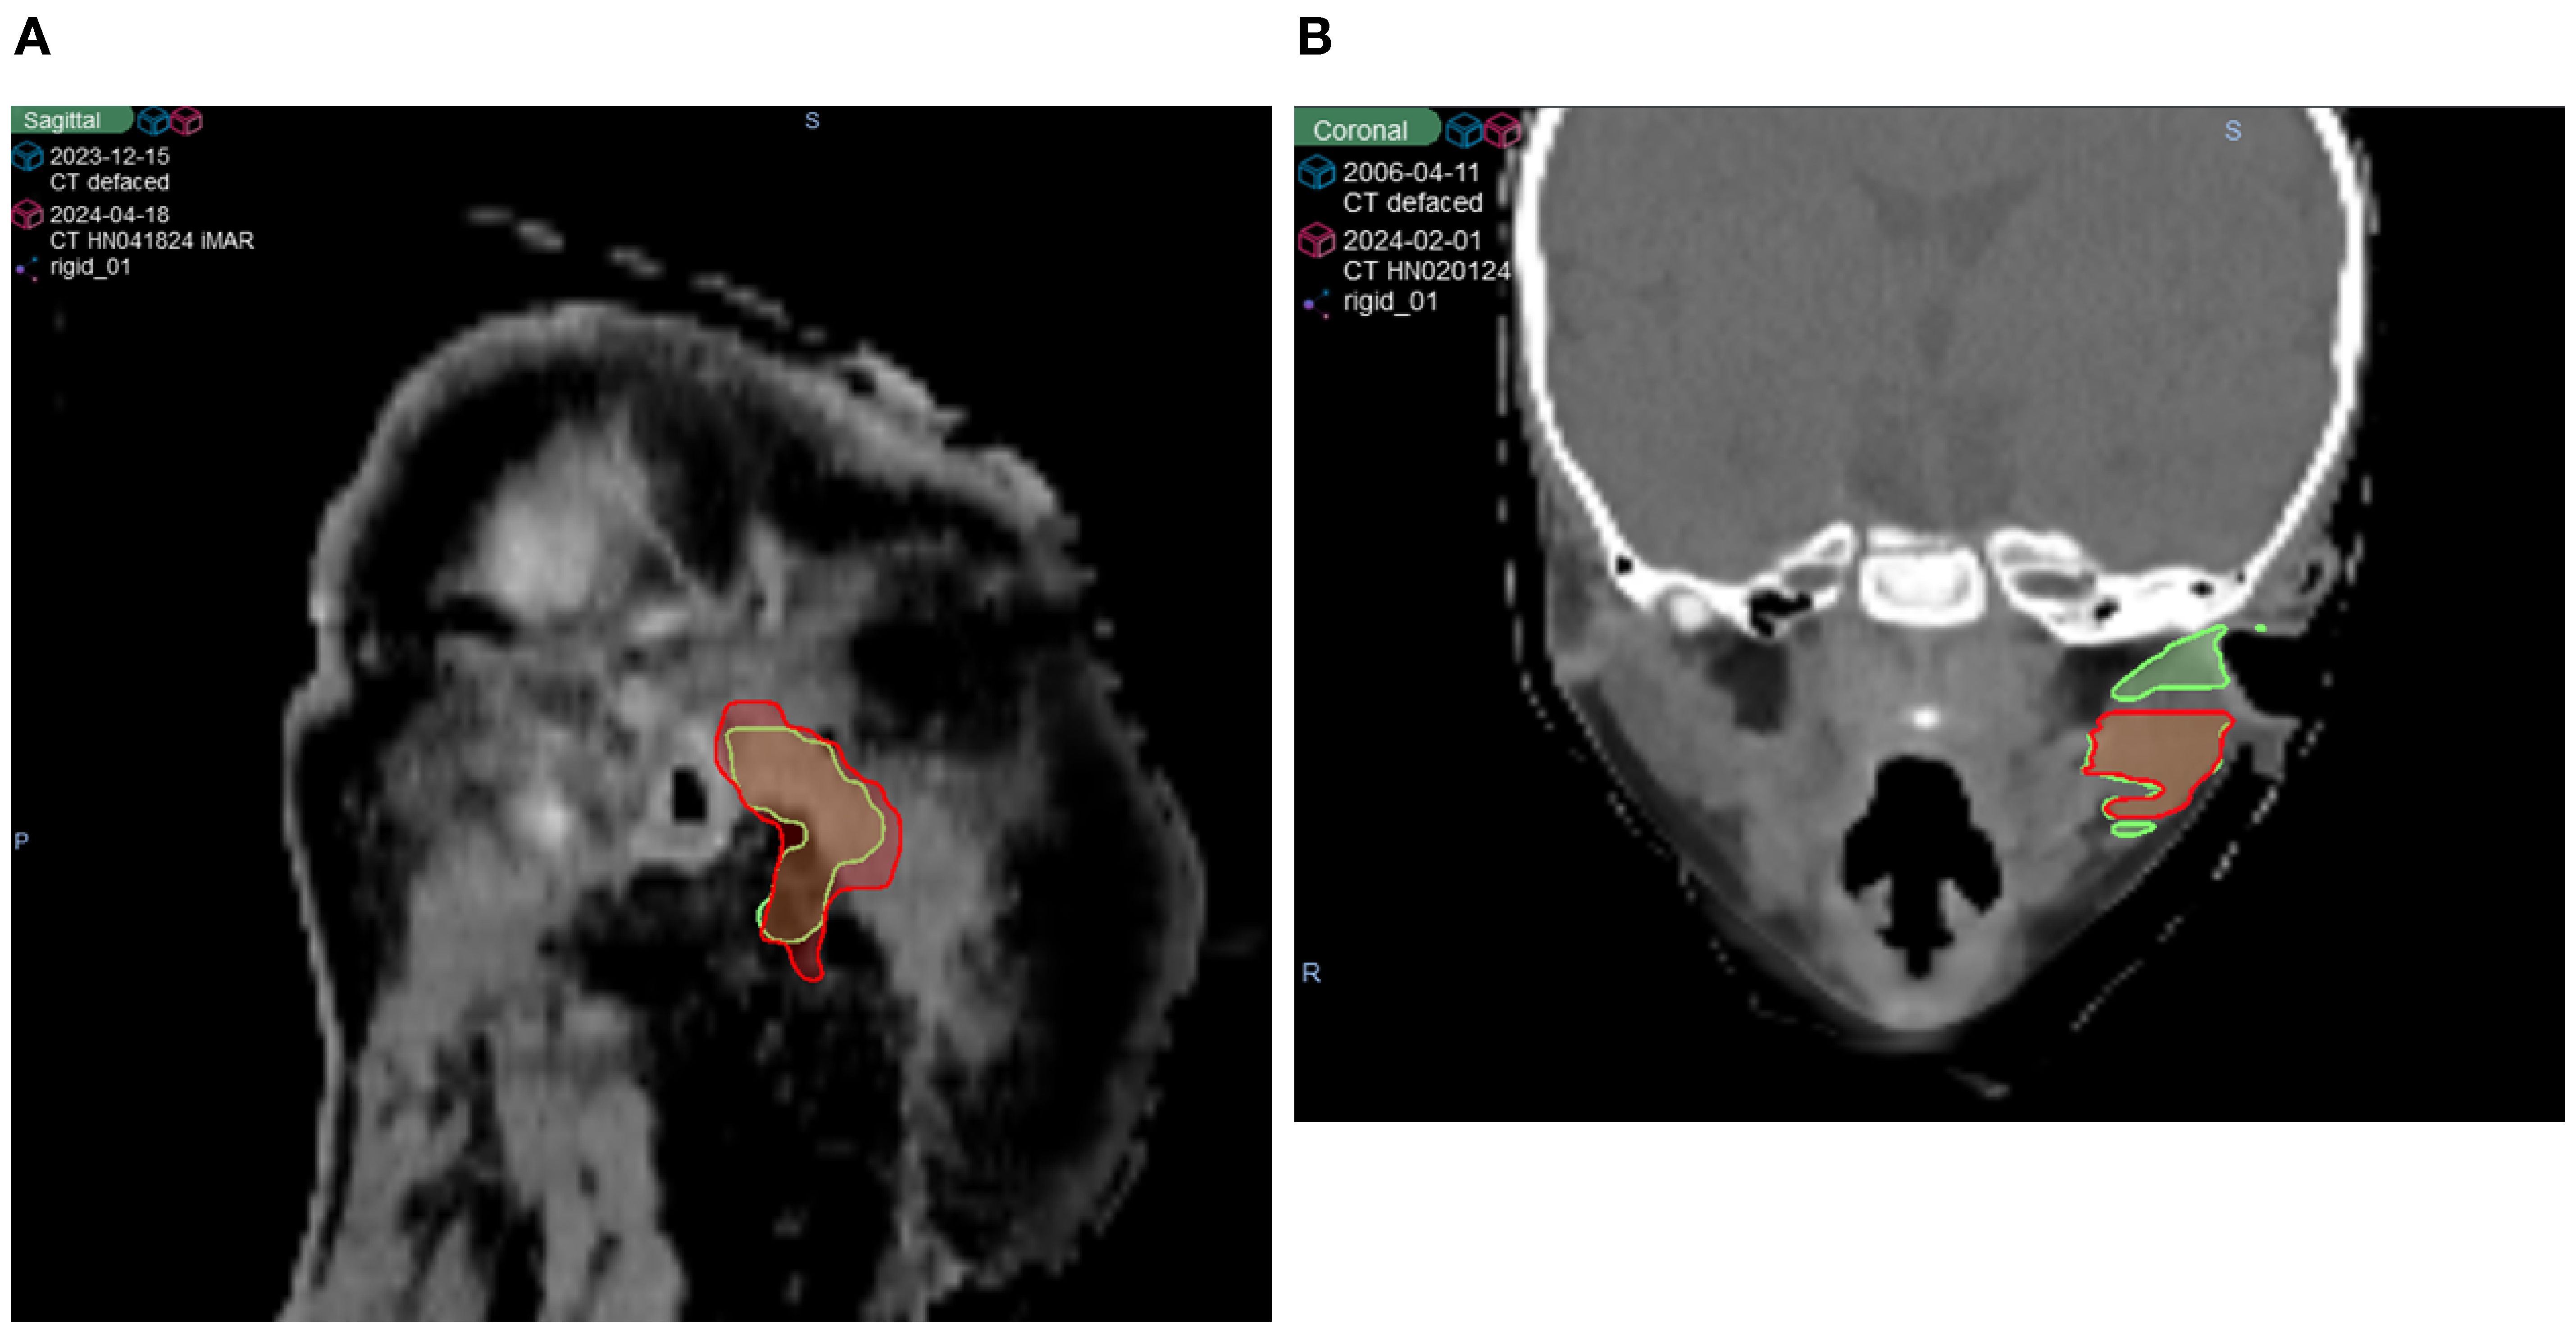

As shown in Figures 3A–C, while many structures demonstrated strong overall robustness to the defacing operation—achieving >0.90 DSC, >0.95 SDSC_2mm, and <2 mm HD95 in most cases—some outliers were notably affected. One such case is illustrated in Figure 4, where the Parotid_R was segmented using INTContour (Figure 4A) and the Parotid_L using AccuContour (Figure 4B). These two cases exhibited a large discrepancy in their HD95 values, with INTContour and AccuContour achieving HD95 measurements of 9.58 mm and 11 mm, respectively. This discrepancy underscores that while defacing does not significantly impact most structures, certain cases—particularly those involving larger or more complex anatomies like the mandible—may still experience notable segmentation variability.

Figure 4. Two patient cases illustrating poor performance by both AI segmentation tools. The original (green) and defaced (red) contours are overlaid on the defaced CT. (A) The right parotid segmented using INTContour, with a Dice score of 0.79, HD95 of 9.58 mm, and SDSC_2mm of 0.78. (B) The left parotid segmented using AccuContour, with a Dice score of 0.83, HD95 of 11 mm, and SDSC_2mm of 0.80.